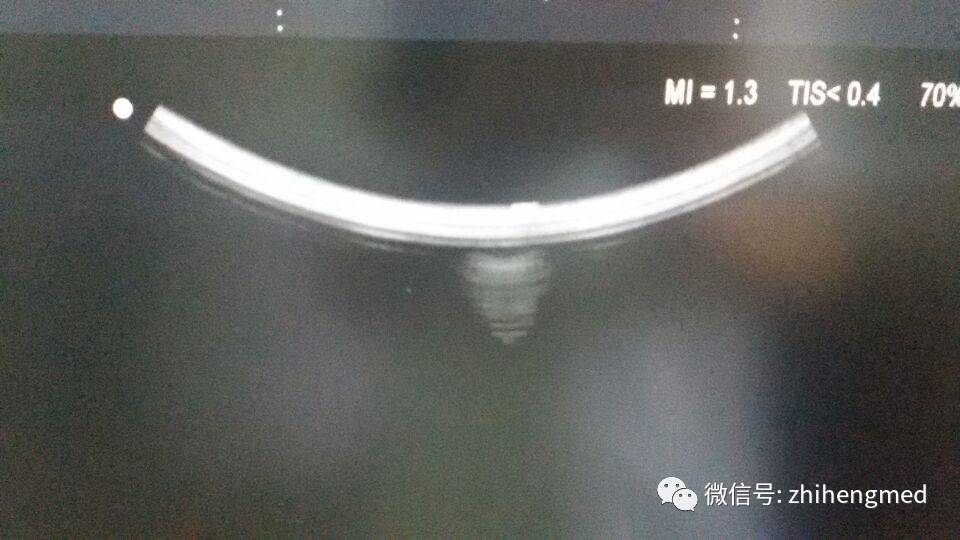

机器所有探头均无图像,初步排除探头本身故障可能,仔细辨听探头有正常工作声音,基本可排除探头接口板及TX发射板故障可能。测量机器电源各电压输出,除高压偶尔输出70V(标注正常值为80V)外,其它电压输出均正常,电源故障可能性较小。因此故障可能性较大为RX板、BF板、数模转换及处理数据部分板块。最后更换负责数模转换功能的DSC板,故障排除。